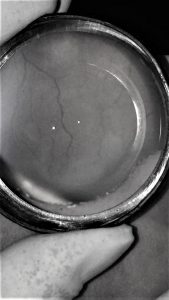

Vascularización incompleta